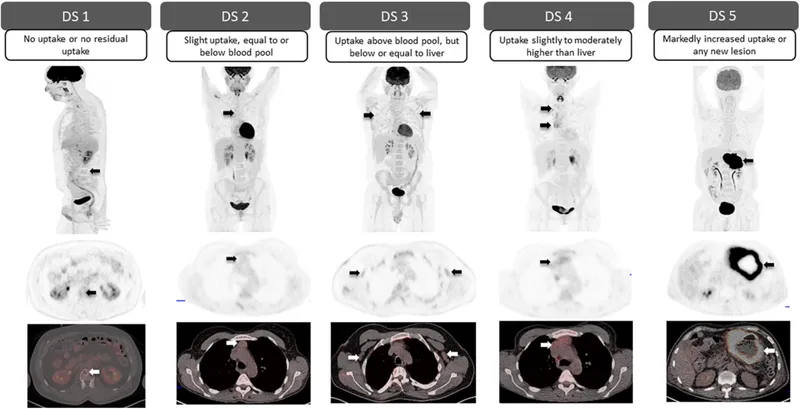

- PET-adapted therapy: Deauville score ≤3 predicts >90% cure